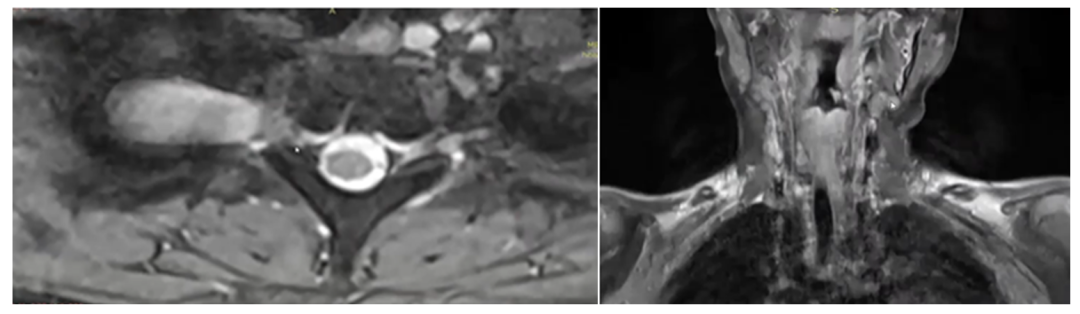

随着年龄增长,轩轩身上的咖啡斑和色素沉着越发明显,潜藏在体内深部的瘤体也明显增大,并且逐渐出现了新发病灶,包括颈部、脊椎旁,骶管、盆腔等。

患儿颈胸段、腰段等多处出现结节